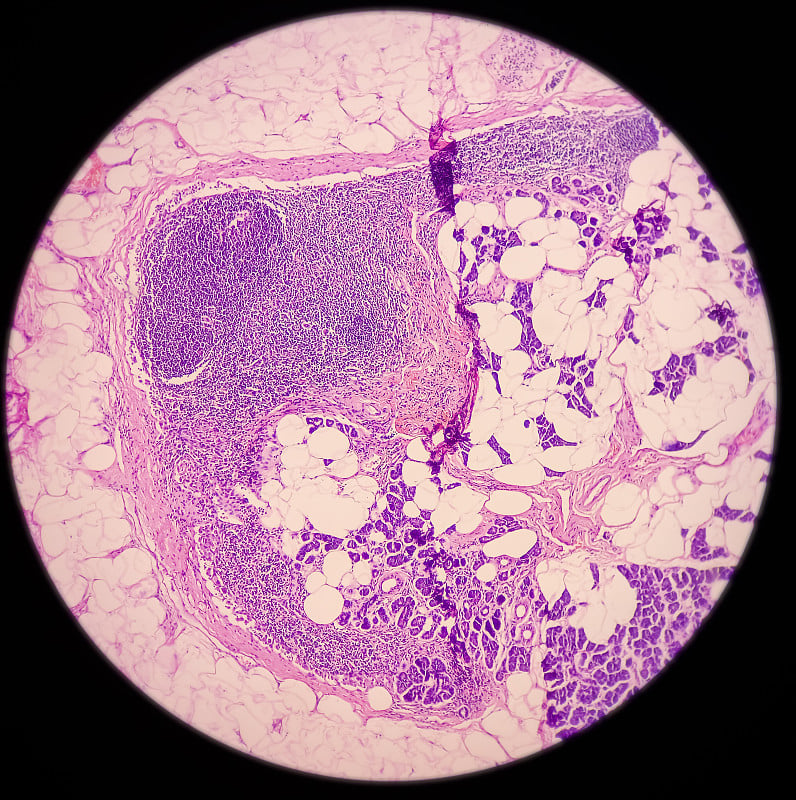

在显微镜下观察肝脏详情